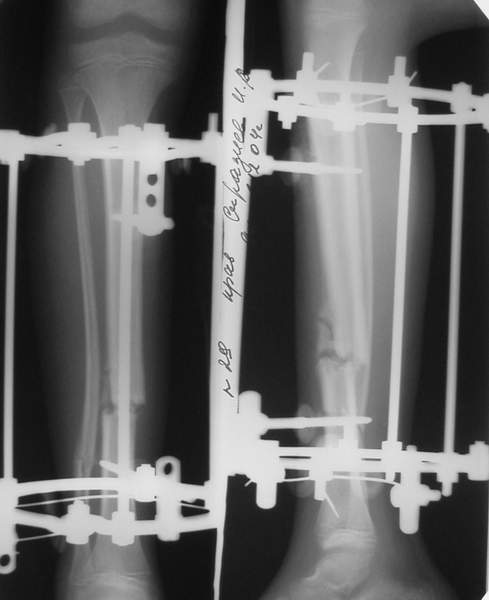

Под рукой прилагаемый пример. Как видите, "стриптиз-аппарат" (шутка проф. З.К.Башурова): 3 кольца-2 кольца-2 полукольца. В случае, который представил Евгений, характер повреждения позволил бы сразу использовать аппарат на основе 2 колец; в крайнем случае прокс. опора м.б. демонтирована сразу после репозиции.

В аттачтах №№ 1 и 2 - примеры, когда 2 кольца не позволили послеоперационно

исправить смещение фрагментов большеберцовой (по ширине и вальгусное).

А казалось бы (#2) - поиграй на штангах и все влетит.